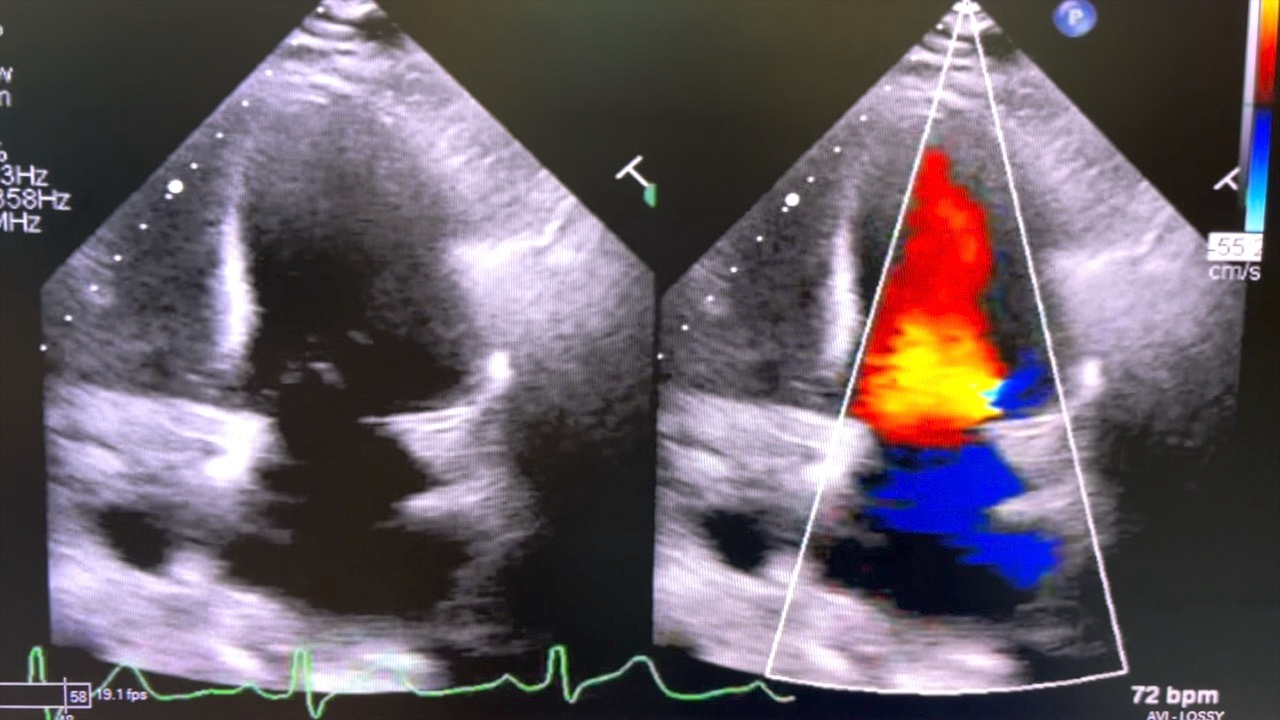

TGH saves more lives with new transplant technology but needs heart donations

Stassy Olmos